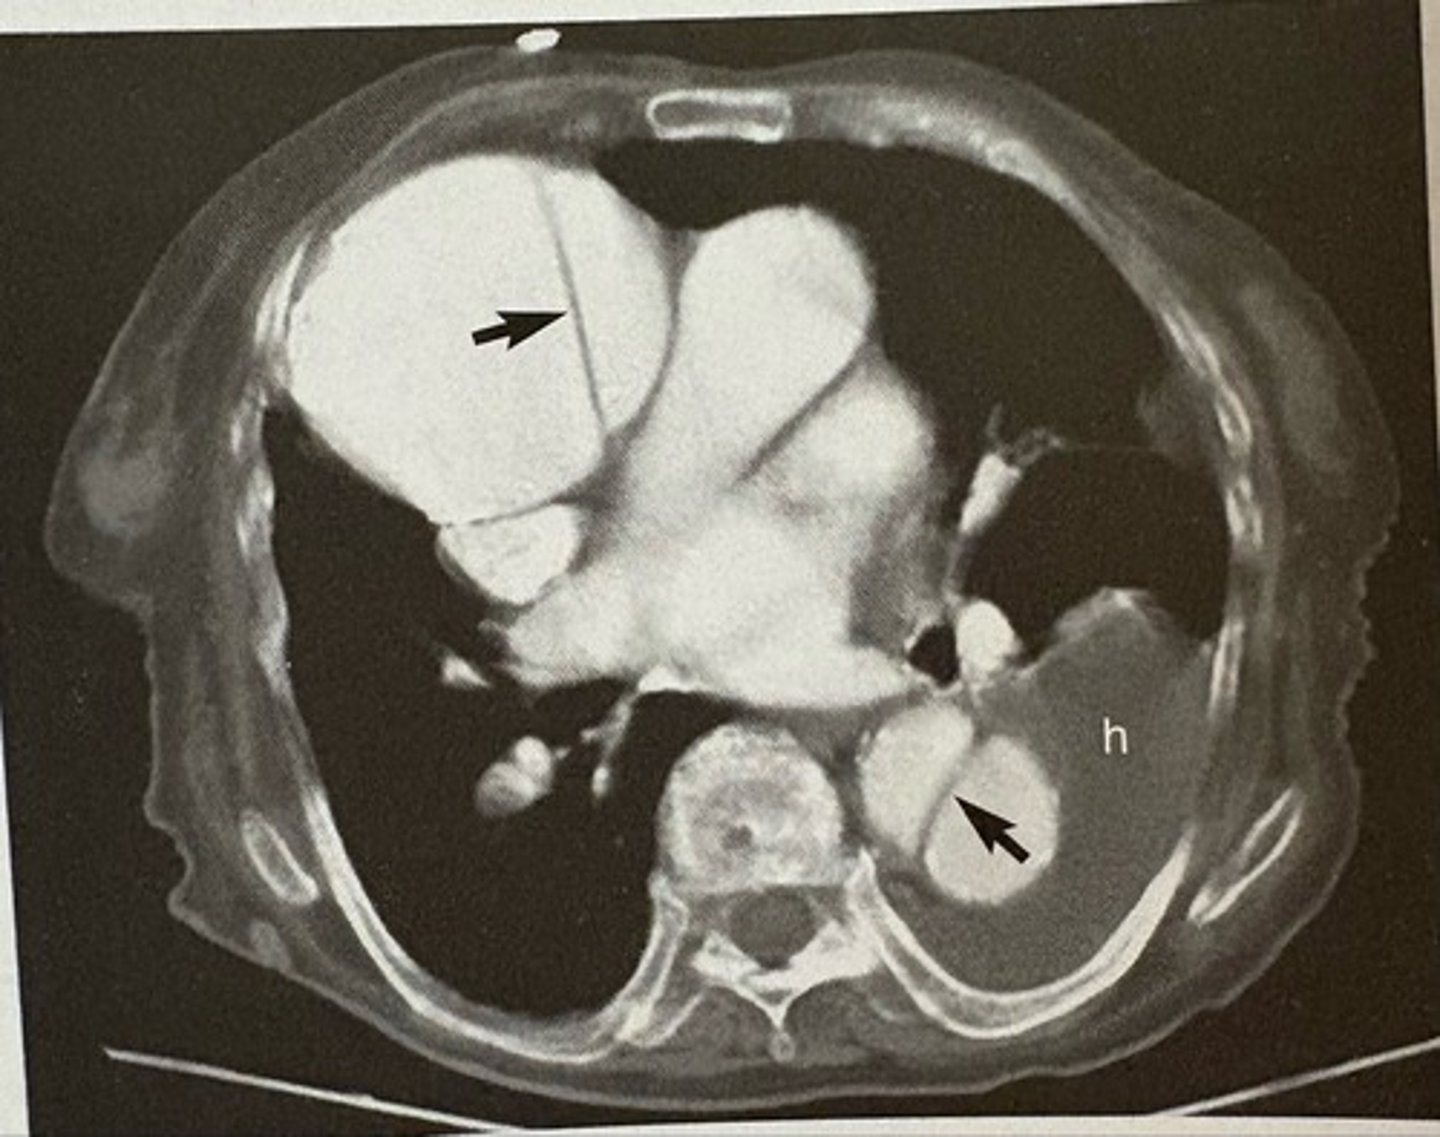

pericardial effusion

what pathology is present?